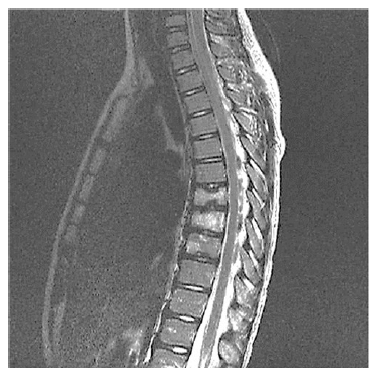

Um paciente de 15 anos de idade com queixas crônicas de dorsalgia (mais de um ano), leva à consulta ressonância magnética de coluna total apresentada. Não há outras queixas.